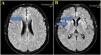

(A) Brain MRI images with Axial FLAIR sequence at the centrum semiovale show a small cortical hypersignal in the superior frontal gyrus bilaterally (blue arrow). (B) Brain MRI images at the basal ganglia level also demonstrate a symmetric and bilateral hypersignal in the caudate and putamen, as well as in the superior frontal gyri (blue arrow).

Case reportA 59-year-old man was diagnosed with HIV associated with Pulmonary Tuberculosis (TB) in late 2012 (at age 48) through ELISA and Western Blot serological tests, as well as a sputum culture for Acid-Fast Bacilli (AFB). He initially received treatment for TB, followed by Antiretroviral Therapy (ART) two weeks later, consisting of tenofovir (TDF), lamivudine (3TC), and efavirenz (EFV). Laboratory tests before starting ART showed a CD4 count of 18 cells/mcL (4 %) and a CD8 count of 203 cells/mcL (45 %), with a Viral Load (VL) of 224,906 copies/mL (Log=5.35). After completing TB treatment, his CD4 count increased to 167 cells/mcL (17.9 %), and his VL decreased to 82 copies/mL (Log=1.91). The patient developed Immune Reconstitution Inflammatory Syndrome (IRIS) with cervical lymphadenitis, which was managed with aspiration, and experienced persistent peripheral neuropathy during TB treatment, requiring pyridoxine supplementation. During this period, he also developed systemic arterial hypertension, type 2 diabetes mellitus, dyslipidemia, and keratitis related to past pterygium surgery. After 11-years of regular antiretroviral therapy, which was later switched to lamivudine and dolutegravir, he maintained persistent undetectable HIV viremia and adequate pharmacological control of systemic arterial hypertension, type 2 diabetes and hypercholesterolemia, using losartan 50 mg/day, metformin 1g/day, and atorvastatin 10 mg/day. He persistently reported bilateral 'boot distribution' paresthesia, attributed to an adverse reaction to isoniazid. During a routine follow-up on May 8, 2023, he mentioned that his partner had been complaining about him forgetting personal items, such as his wallet and car keys, despite the patient’s own disagreement. At this time the International HIV Dementia Scale scored seven points, and a brain MRI was recommended. Unfortunately, he did not undergo the requested brain MRI and returned only three months later, experiencing a sudden worsening of symptoms, including increased neuropathy, weight loss, social withdrawal, and somnolence. Neurological examination revealed temporal disorientation, ataxia, a left Babinski sign, hyperreflexia in the right patellar tendon, exhausted clonus in the right foot, and dysdiadochokinesia. Myoclonus was not present. Hospitalization was recommended, when evaluated by a neurologist, and MRI (in August 9) showed a restricted diffusion hypersignal located bilaterally in the insula, basal ganglia, and anterior cingulate cortex (Fig. 1). Seventeen days after this first and brief hospitalization, MRI showed symmetric and bilateral hypersignal in the caudate and putamen, as well as in the superior frontal gyri (Fig. 2). Concurrent laboratory tests showed no abnormalities, including a non-reactive VDRL and normal renal, thyroid, and liver function. A lumbar puncture was also performed, and partial analysis of the Cerebrospinal Fluid (CSF) revealed normal cell counts and glucose and protein levels. Tests for pyogenic bacteria, fungi, and tuberculosis and PCR for herpes simplex virus types 1 and 2 were all negative. RNA PCR for HIV in the CSF was also negative. In addition, CSF autoantibodies for autoimmune and paraneoplastic encephalitis and 14-3-3 protein analyses were requested. At this point, we suspected rapidly progressive dementia, with prion disease and immune-mediated encephalitis considered as the main possibilities. Due to the delay in obtaining the 14-3-3 protein results, the patient was hospitalized for pulse therapy with methylprednisolone (1.0 g/day for 5-days), followed by intravenous immunoglobulin (IVIG – 2.0 g/kg for 5-days). During the second hospitalization (lasted 56-days), repeat MRI showed the same abnormalities described above, but the patient’s condition worsened, with further memory decline, spastic tetraparesis, hypophonia, and bradykinesia in both the upper and lower limbs. Furthermore EEG video was performed due to its longer duration in an attempt to capture changes characteristic of CJD, such as triphasic waves. The disease progression was rapid, leading to a state of akinetic mutism. A Gastrostomy Tube (GTT) was placed due to dysphagia. The patient developed a fever caused by aspiration pneumonia, which was treated with antibiotics, and was discharged with the GTT, spastic tetraparesis and akinetic mutism. After 60-days, the 14-3-3 protein results were received, revealing high titers, and the family was consulted about initiating palliative care to avoid invasive measures. During his course, the patient underwent 3 EEGs, all of which revealed only nonspecific slowing. RT-QuIC analysis of the CSF was positive. He passed away 6-months after the onset of neurological symptoms.

Alongside the clinical presentation, complementary examinations play a key role in the diagnosis of CJD3,13. Brain MRI typically reveals lesions characterized by Diffusion-Weighted Imaging (DWI) hyperintensities and signal abnormalities on FLAIR and T2-weighted sequences, particularly in the cerebral cortex and basal ganglia, as observed in the present case14 .Electroencephalogram findings, though limited in sensitivity, may show triphasic waves or periodic complexes, which can contribute to the diagnosis15. Cerebrospinal fluid analysis can help detect elevated levels of proteins such as 14-3-3, tau, and p-tau, which are associated with the disease16. Furthermore, the identification of pathological prion protein through RT-QuIC in nasal mucosa or CSF is notable for its high specificity17.